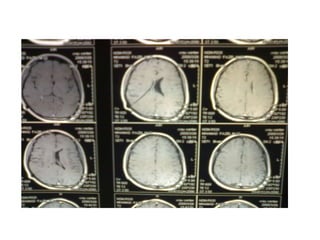

Investigation U ltrasonography to visualize the ventricular system(when the anterior fontanelle is patent). Also for antenatal diagnosis CT and /or MRI of the head; it is important to exclude any abnormal masses and to study the size and the shape of the ventricles, and some time needs contrast study.  LP in cases of communicating hydrocephalus for both diagnostic and therapeutic…..( NPH)

NPH A broad based shuffling gait (gait apraxia)  Dementia (memory loss and a generalized slowing of thought) Urinary incontinence

In addition to CT and MRI  lumbar puncture (LP) is important  in the diagnosis of NPH

Investigation U ltrasonographyto visualize the ventricular system(when the anterior fontanelle is patent). Also for antenatal diagnosis CT and /or MRI of the head; it is important to exclude any abnormal masses and to study the size and the shape of the ventricles, and some time needs contrast study. LP in cases of communicating hydrocephalus for both diagnostic and therapeutic…..( NPH)

NPH A broadbased shuffling gait (gait apraxia) Dementia (memory loss and a generalized slowing of thought) Urinary incontinence

In addition toCT and MRI lumbar puncture (LP) is important in the diagnosis of NPH